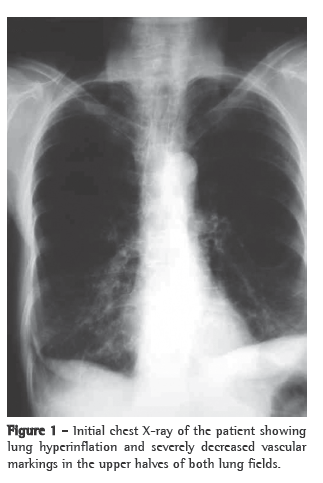

A 69-year-old female smoker (30 pack-years) homemaker from São Sepe, Brazil, presented with rheumatoid arthritis for 14 years. The patient had undergone a thyroidectomy 20 years before. The epidemiological history was not clear regarding possible fungal exposure. The patient had been experiencing progressive dyspnea, productive cough, recurrent respiratory infections, loss of appetite, nausea and weight loss for 4 years. The patient was using levothyroxine, calcitriol and prednisone 15 mg/day; however, she had previously used methotrexate. Physical examination revealed that the patient had lost weight (patient weight at the time was 30 kg, and body mass index was 14 kg/m2). No cervical lymph node enlargement, supraclavicular lymph node enlargement or digital clubbing was observed. Pulmonary auscultation revealed only a diffuse reduction in breath sounds. A chest X-ray taken at the onset of the condition (4 years before) showed lung hyperinflation and severely decreased vascular markings in the upper halves of both lung fields (Figure 1). An HRCT scan had revealed paraseptal emphysema, cavities and destruction of the lung parenchyma, predominantly in the upper lobes (Figure 2). Arterial blood gas analysis and the tuberculin skin test revealed no abnormalities.